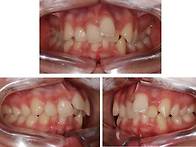

이수행 18.05.13안녕하세요. 공주 미소담 치과입니다. '공주치과'로 인터넷 검색을..